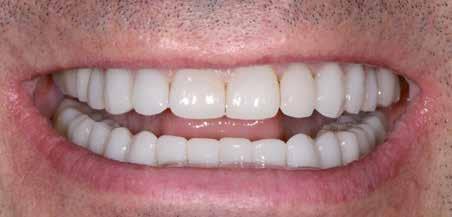

A fogszabályzó kezelések egyik legfontosabb célja, hogy elérjük a lehető legharmonikusabb interokkluzális fogérintkezéseket, továbbá az állcsont relációs helyzetének frontális és szaggitális síkban is megfelelőnek kell lennie. A fogszabályzás befejezésekor a fogpozícióknak nem orthodonciai, hanem protetikai szempontok szerint kell ideálisnak lenniük. Az Invisalign ClinCheck szoftver (Align Technology) segítségével a protetikus az orthodontussal együtt meg tudja határozni azokat a végső fogpozíciókat, amelyek a lehető legjobb végeredmény biztosításához elengedhetetlenek. Bizonyos klinikai paramétereket, mint a fogak klinikai koronájának nagyságát, az egyes fogak fogíven belüli optimális pozícióját, a fogívek egymáshoz viszonyított helyzetét, a fogak között látható rések nagyságát, a frontfogak tengelyének dőlését, az overjet és overbite mértékét már a kezelések megkezdése előtt pontosan definiálni kell. Ezeket az adatokat viszont csak a tervezett végleges fogpótlás ismeretében lehet meghatározni, ezért van szükség az orthodontus és a protetikus szoros együttműködésére.

A közös munka során az egyik legelső és legfontosabb feladat annak a meghatározása, hogy a páciens jelenlegi maximális interkuszpidációs helyzete (IKP) milyen mértékben tér el az

32 e-Journal DENTAL HÍREK

33 VII. ÉVFOLYAM – 2024. 3. SZÁM

1-4. ábra: Kiindulási állapot. 5. ábra: ClinCheck szoftverrel történő kiértékelés. A kiindulási és az orthodonciai kezelés végén elérni kívánt állapot összehasonlítása. 6-9. ábra: Az orthodonciai kezelés végén elért állapot.

10. a-c. ábra: Módosult passzív erupció jelenlétének diagnosztizálása radiológiai felvételek segítségével (altered eruption radiographic technique; AlteRx).

11. a-b. ábra: A gingivectomia és frenulectomia elvégzését követően látható állapot.

12. a-d. ábra: Az állcsont relációs helyzetét a helyreállítás befejezése után elérni kívánt állapotot bemutató mock-up felhelyezését követően rögzítettük az arcív és a harapási sánc segítségével.

állcsontok centrális relációs helyzetétől (CR). Ezt a helyzetet úgy is leírhatnánk, mint az a legideálisabb állkapocs-ízületi helyzet, amely elérését követően a lehető legkedvezőbb állkapocshelyzetből történhet meg az alsó és felső fogív végleges fogpótlásokkal történő helyreállítása. Ennek a meghatározásakor a frontális és a szaggitális síkban megfigyelhető komponenseket is figyelembe kell venni. Az optimális állcsont relációs helyzetének megállapítása előtt elengedhetetlen az állkapocs-ízület beprogramozása, a rágóizmok lazítása, és

állkapocs-ízületi rendellenességek fennállásának ellenőrzése. Amennyiben állkapocs-ízületi rendellenességeket diagnosztizálunk, úgy először gnatológiai terápiát alkalmazunk, melynek célja a rágóizmok működésének és az állkapocs-ízület egészségének helyreállítása. A komplex rehabilitációs beavatkozások kivitelezésének megtervezését csupán az új, biológiai és funkcionális szempontokból ideális állkapocs-ízületi helyzet elérését követően szabad megkezdeni.

34 e-Journal DENTAL HÍREK